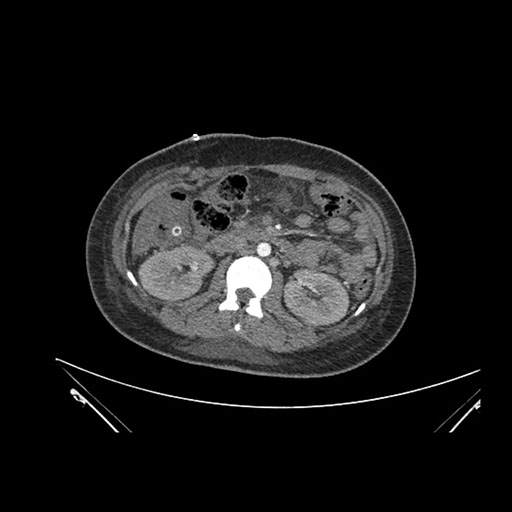

Imaging Analysis

Look through the patient's CT scan to identify any areas of concern for the necessary procedure.

Coronal Venous